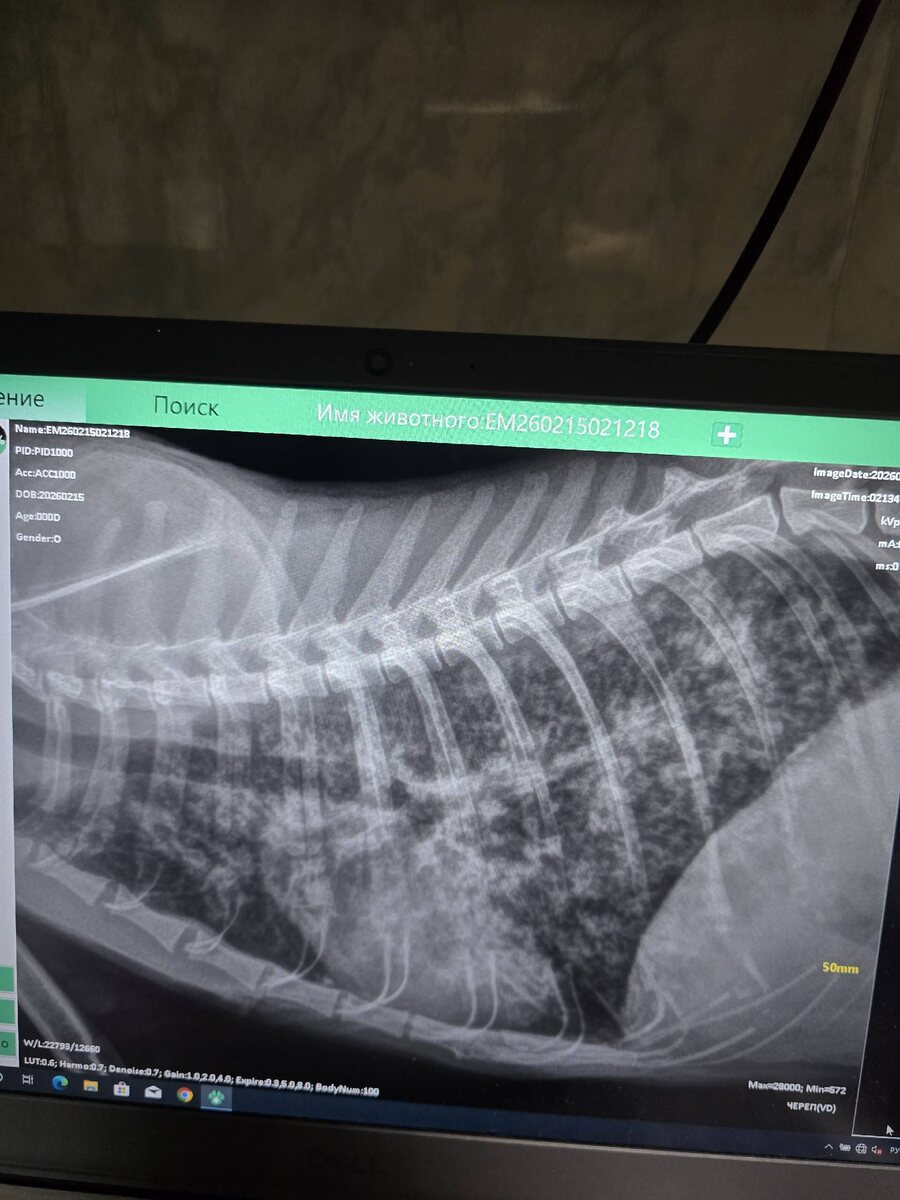

Вчера она была у врача. Жалобы у нас были на одышку, новообразование на молочной железе. В общем, всё плохо. У Мани онкология. Метастазы уже. Понятное дело, что лечения никакого нет. Назначили поддерживающую терапию, гормоны. Мане очень нужен корм роял канин Gastrointestinal влажный в паучах. Будем благодарны, если пришлете его для этой кошечки 🙏

Новости по Мане. Вчера она была у врача. Жалобы у нас были на одышку, новообразование на молочной железе.

В общем, всё плохо. У Мани онкология. Метастазы уже.